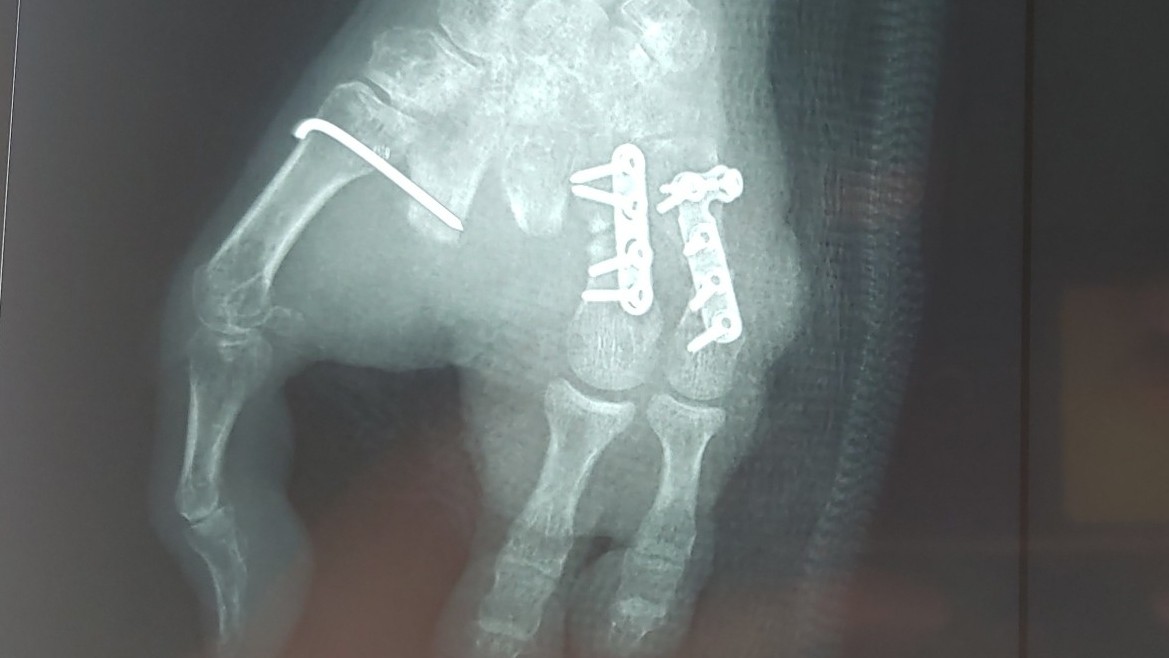

10 phút, cứu bệnh nhân sốc đa chấn thương

Y tế 24h - 15/09/2022

Tối 14/9/2022, BVĐKTƯ Cần Thơ cho biết, các bác sĩ đã cứu sống bệnh nhân nguy kịch do bị bức tường đổ đè lên người sau 10 phút cấp cứu.